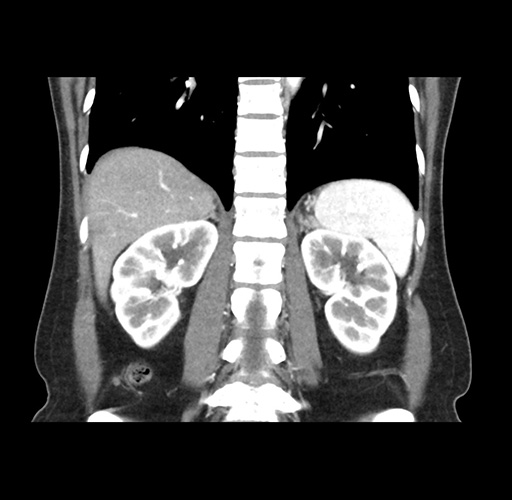

Imaging Analysis

Look through the patient's CT scan to identify any areas of concern for the necessary procedure.

Based on your CT findings, which issue(s) would give reason for "planned slowing down moment(s)" in this case?

Considering a standard left lateral sectionectomy procedure, what step(s) of the operation would you do differently in this case ?